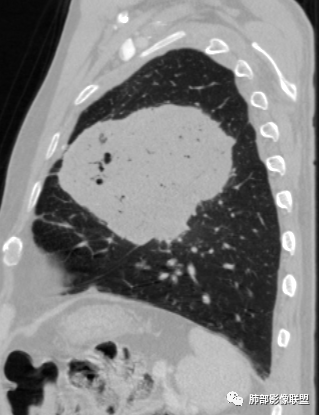

原发性肺肉瘤样癌(PSC)一组临床罕见的肺部肿瘤,属于上皮细胞源性肿瘤,仅占肺部恶性肿瘤的0.3%~4.7%。为含有肉瘤形态细胞或肉瘤样分化的非小细胞肺癌,癌成分多为鳞癌或腺癌,肉瘤成分最常见的是纤维肉瘤。

肺肉瘤样癌的CT表现主要特点:

1)部位:周围型或中央型软组织肿块,以周围型为多见,且肿瘤多位于肺上叶。如本例:该肿瘤位于左肺上叶。

2)大小及形态:由于本病恶性程度高,早期症状不明显,发现时肿块均较大。如本例病变巨大。

3)肿块边界和边缘:多较清楚,呈圆形、类圆形,且由于肿块生长速度不均匀,可见分叶,毛刺少见。有报道肿块周围毛玻璃影是多形性癌特征表现。

4)密度:肿块平扫为软组织密度,由于体积较大,内部常见大片状坏死,可出现不规则厚壁空洞或坏死内多发无壁小空洞,坏死多不均匀:坏死灶内可见如柳絮样的斑片样强化灶,坏死边缘与非坏死区分界不清本例坏死较明显,密度不均匀。

5)肿瘤强化方式:肺部恶性肿瘤强化程度与其血供丰富程度相关,血供丰富多强化明显,反之则较差。由于PSC 周边实性部分富血供及内部黏液变性、坏死,增强后肿块多数呈轻-中度边缘环形强化或不均匀小斑片状强化。国外学者对照病理发现肿瘤细胞或胶原组织增强扫描时强化,无强化的低密度区代表了黏液样变性区和出血坏死区。